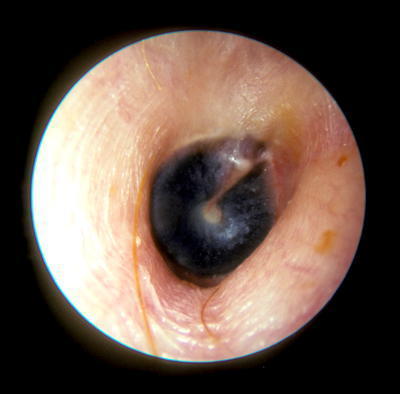

Vous faites un examen du tympan droit. Vous trouverez ci-dessous plusieurs exemples d'otoscopies. Figure 6

Question 8 - Dans le cas d’une fracture du rocher à droite, quelle(s) est (sont), parmi les otoscopies présentées ci-dessus, celle(s) qui est (sont) compatible(s) avec ce diagnostic à 24 heures du traumatisme ?

Hémotympan : visualisation d’un hématome dans l’oreille moyenne. C’est l’image typique dans le contexte de fracture du rocher

Dans un contexte de fracture du rocher, soit le tympan peut être normal, soit le plus souvent il y a un saignement dans l’oreille moyenne et on constate un hémotympan. Cliniquement, l’hémotympan se comporte exactement comme une otite séromuqueuse (présence de liquide dans l’oreille moyenne), cf. les questions suivantes.